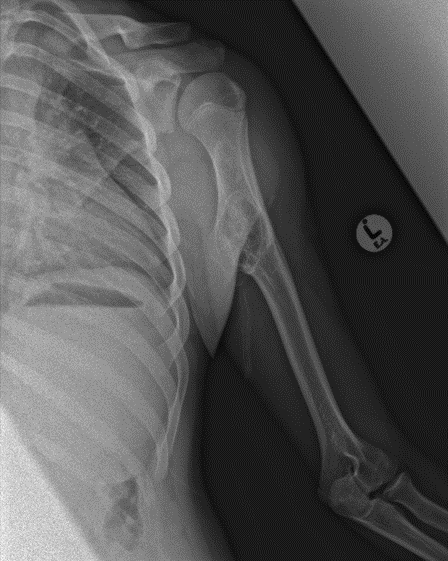

Osteosarcoma. There are many types of osteosarcoma but the most common is the classic intramedullary type which usually originates from the intramedullary cavity of the metaphyseal area of long bones. It is the most common type of bone sarcoma overall. It is most often found in teenagers and young adults. Any pathological fracture in a young person must be considered malignant until proven otherwise. The treatment of an osteosarcoma is classically neoadjuvant chemotherapy – surgery – adjuvant chemotherapy. The biopsy to diagnose bone sarcomas should be done by a sarcoma specialist to prevent difficulties with future surgery and spread of the tumour locally. The 5-year survival for patients with osteosarcoma is between 60% and 70%.